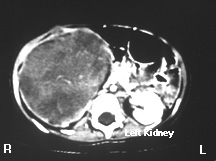

CAT Scan of the Upper Abdomen

This is a contrast CAT scan; intravenous contrast was administered while the images were being obtained. Notice that the left kidney is relatively lighter that the adjacent muscle (posterior to the vertebral body) because contrast is being concentrated in the renal parenchyma. CAT scans can tell us if a kidney is perfused and if it has tubular function. If the kidney were not perfused and functioning, the renal parenchyma would be the same shade of gray as the adjacent muscle.

Notice that the right kidney is enlarged. It doesn't have the uniform light gray that the left kidney has. Instead a relatively heterogeneous mass is present. Notice that there is a thin rim of white around the right kidney.  This is normal renal parenchyma (concentrating the intravenous contrast) stretched over the encroaching tumor.  This child has a Wilm's tumor, the most common renal tumor in children.